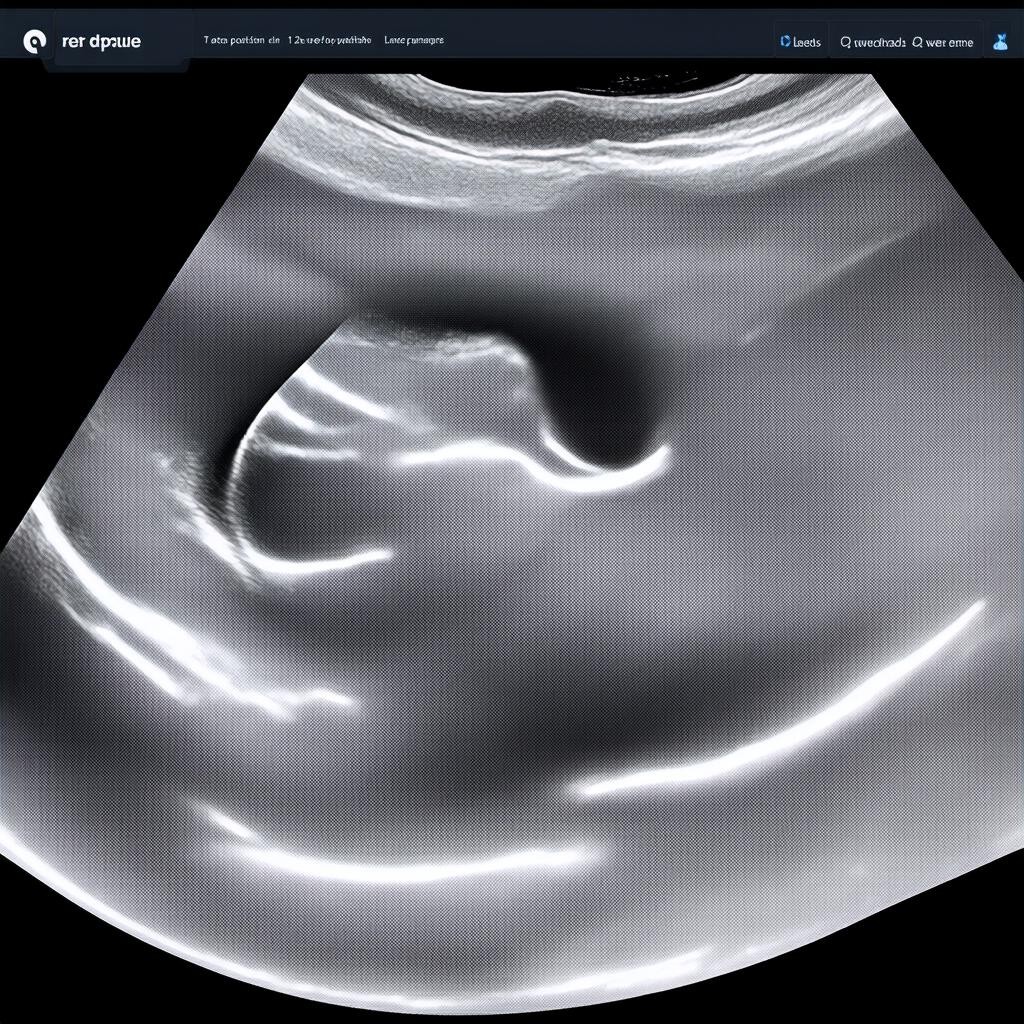

Что смотрят на УЗИ в 12 недель беременности?

УЗИ на 12 неделе беременности — это важный этап пренатальной диагностики. В этот период врач оценивает ключевые параметры развития плода, которые помогают исключить возможные патологии. Это исследование является частью первого скрининга и включает не только ультразвуковую диагностику, но и биохимический анализ крови.